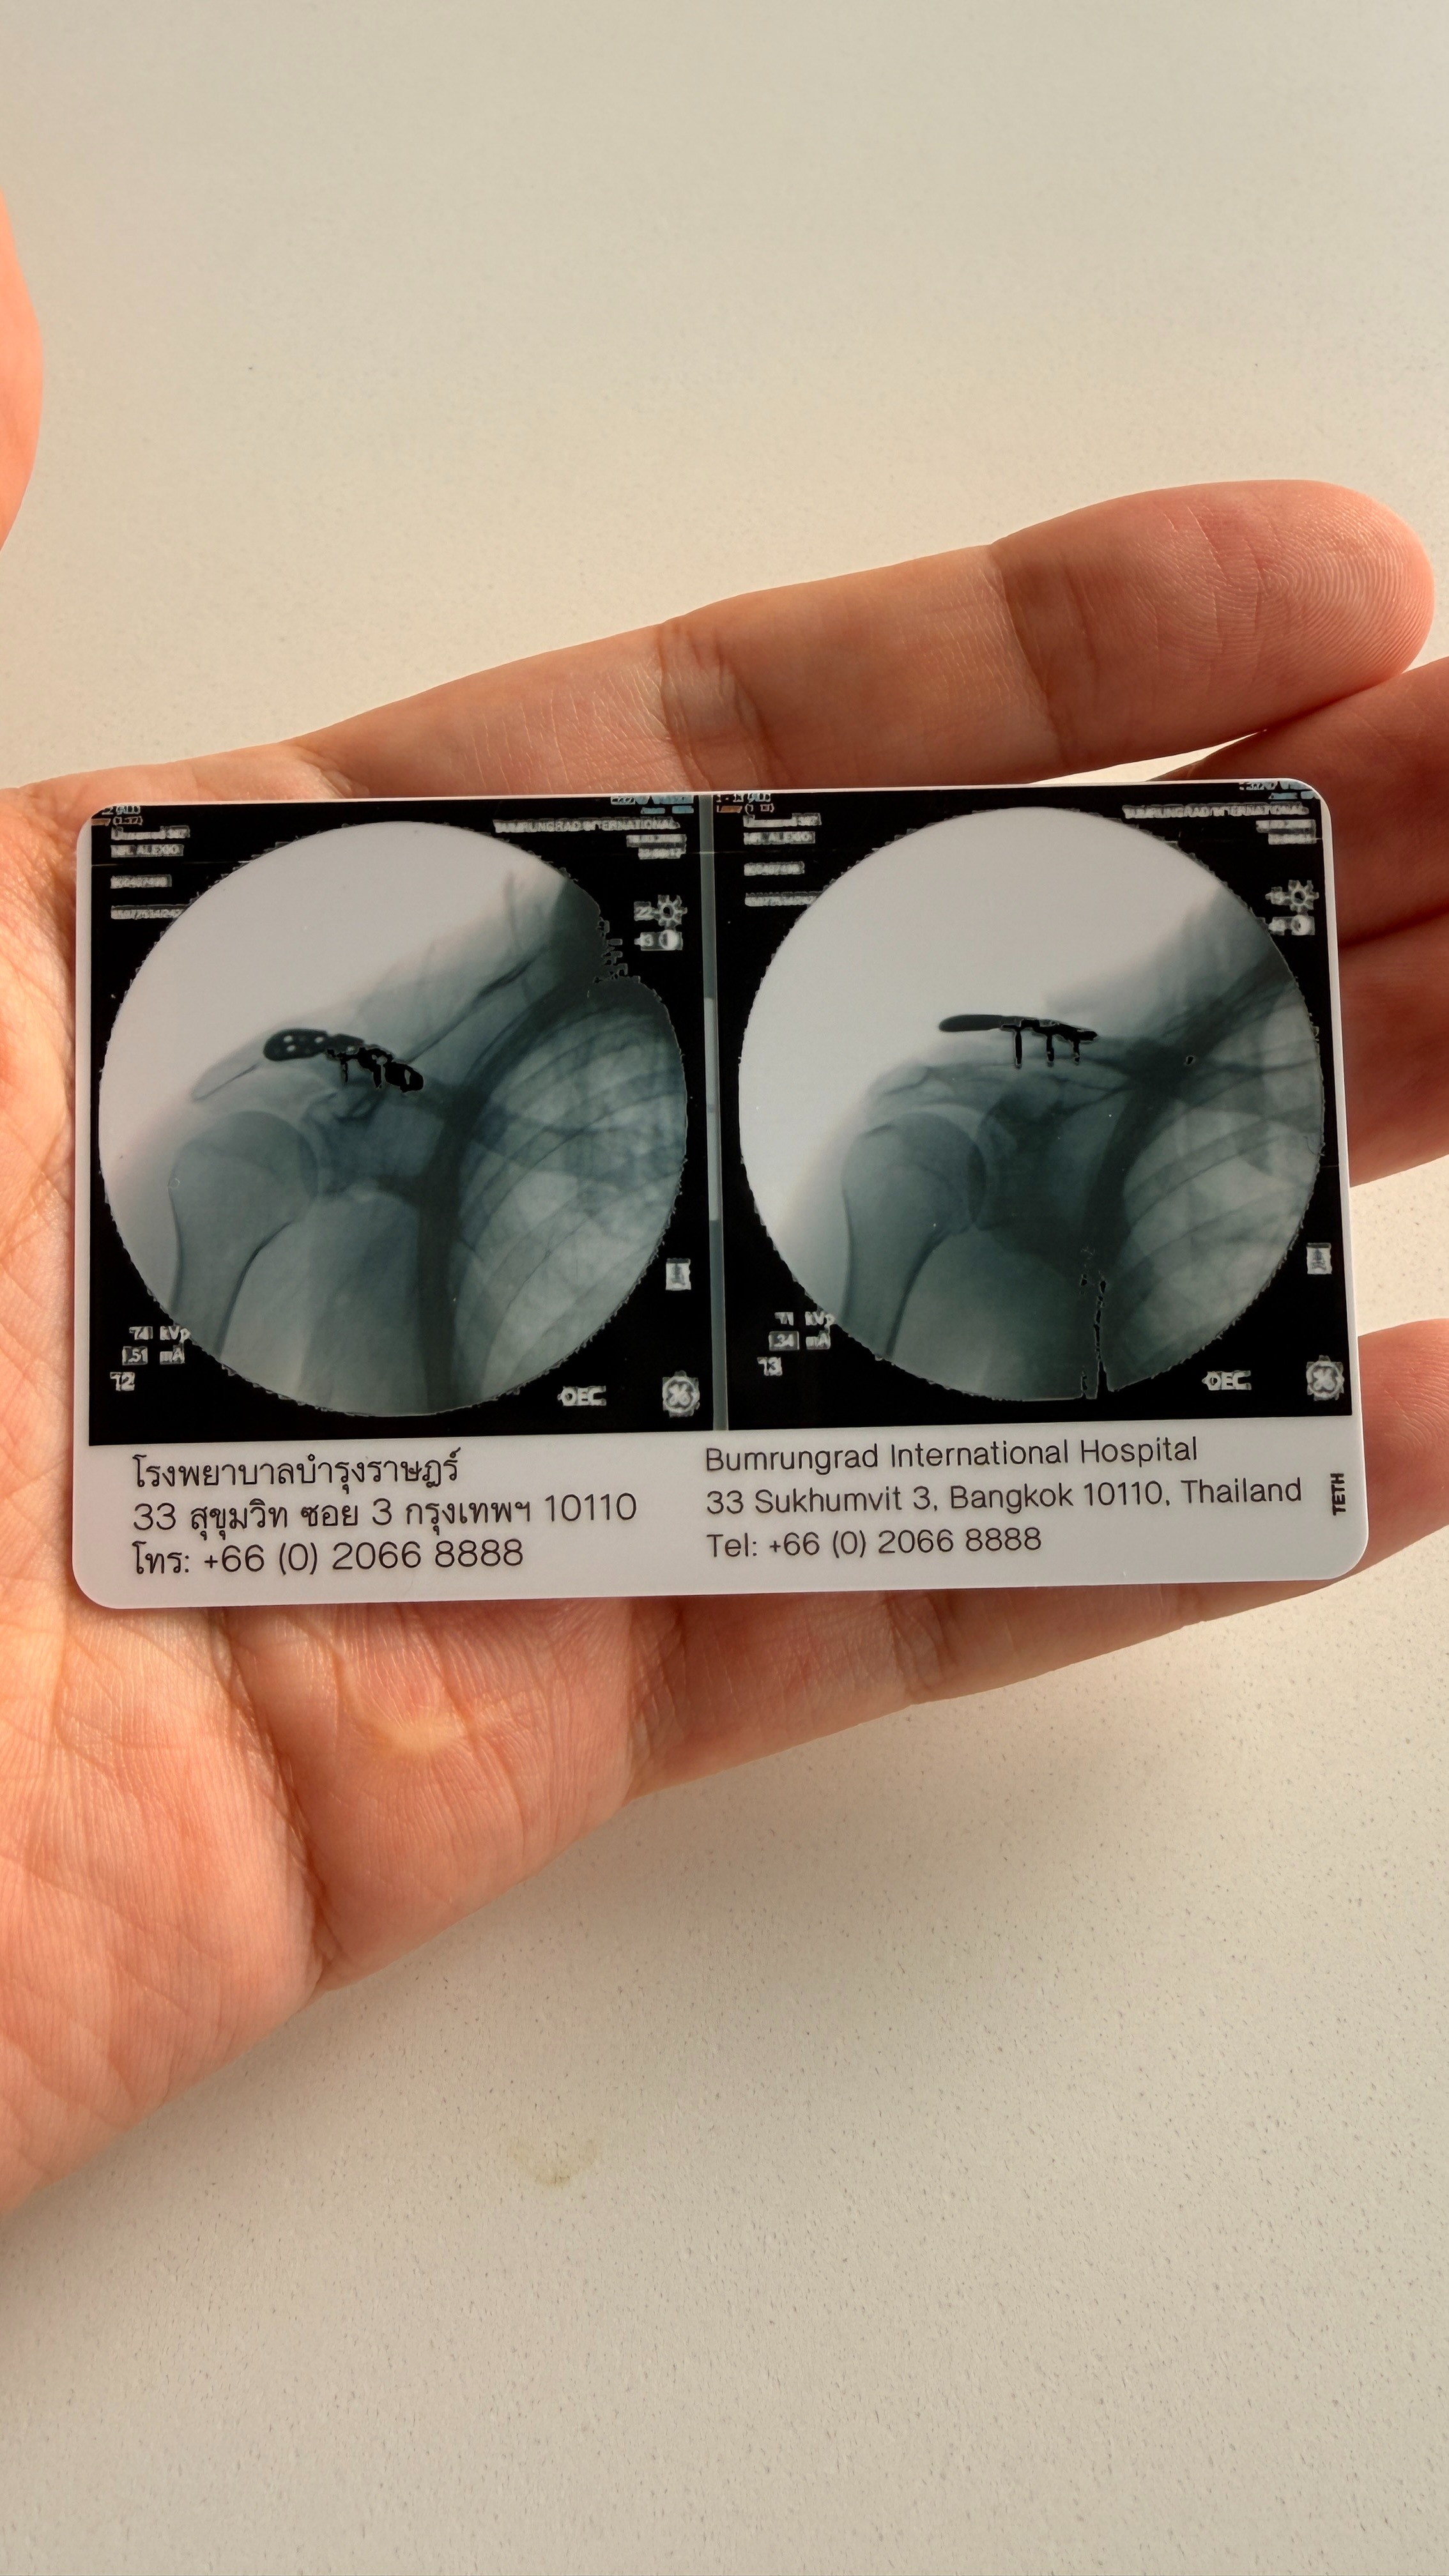

I've already paid 150,000 Baht in hospital bills. My foot was operated on, but the first hospital ignored my broken shoulder — telling me it would "fix itself." It won't. I got a second opinion and now need urgent shoulder surgery.

As a programmer, my hands and arms are everything. Without this surgery, I cannot work. My hand has been permanently numb since the accident. The doctors cannot yet confirm if this will be reversible.

It is uncertain if I will be able to walk again or my hands have permanent damage.